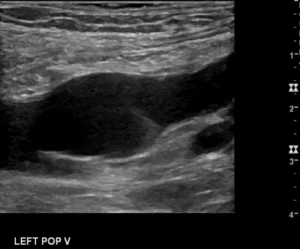

A popliteal vein aneurysm is a dilatation of the popliteal vein. It is uncommon. A busy vascular medicine specialist may see about one a year. Although over 100 cases have been published it is not really clear what to do for patients with a popliteal vein aneurysm. The most dangerous reported problem with this finding…